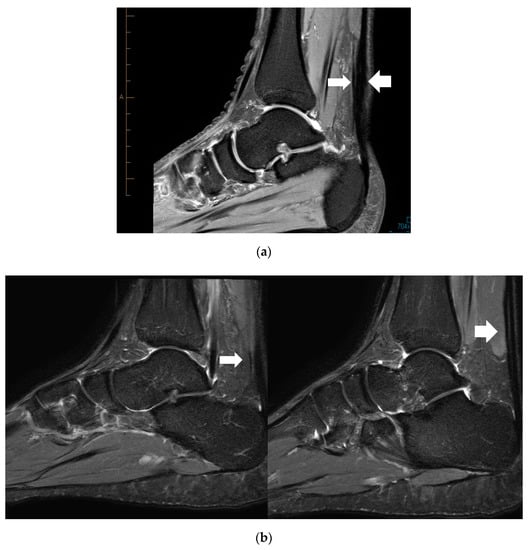

Location of the PT and Mid-AT in relation to their calcaneal insertion is presented in Figure 1 (when these two pathologies are coexisting; n = 10). The mean distance of the two pathologies (PT and Mid-AT) in relation to tendon insertion to calcaneum was similar (Table 1). However, no direct association was observed between the two pathologies and co-located only in one case (Figure 1). The mismatch of Mid-AT and PT pathology locations ranged from −3.7 cm (the Plantaris pathology being more proximal) to 3.4 cm (the Plantaris pathology being more distal). The coefficient of variation (CV = SD/mean × 100) of the distribution of Plantaris pathology (CV = 42%) was greater than the coefficient of variation of Achilles pathology (CV = 17%), which indicates the greater variability in the location of Plantaris pathology than Achilles tendinopathy. The correlation coefficient also revealed a low and non-significant association between the location of two pathologies when they exist together (r = +0.06; p = 0.88). Figure 2 demonstrates the different locations of tendinopathic changes in the Achilles tendon (Mid-AT) and Plantaris tendon (PT) using MRI PD sagittal images.

Figure 2. Proton density (PD) sagittal image showing the location of tendinopathic changes in the Achilles (thick arrow) and the Plantaris tendon (thin arrow) at same level (a), and at different levels (b).